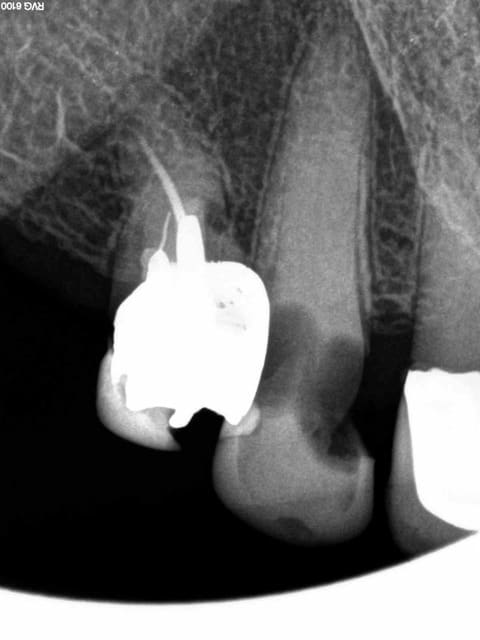

Arrivé un moment ou tu te dis que tu vas l'extraire, mais tu ne le fais pas parceque ca fait 3/4 d'heures que tu cherches ce putain de canal. Et enfin la lumière fut ( c'est le cas de le dire). -)))))

1 nfmvd7 - Eugenol

2 dvdqtt - Eugenol

3 f3ohf3 - Eugenol

4 zmohou - Eugenol

5 j0htr8 - Eugenol

6 e86kdq - Eugenol

7 fbttie - Eugenol